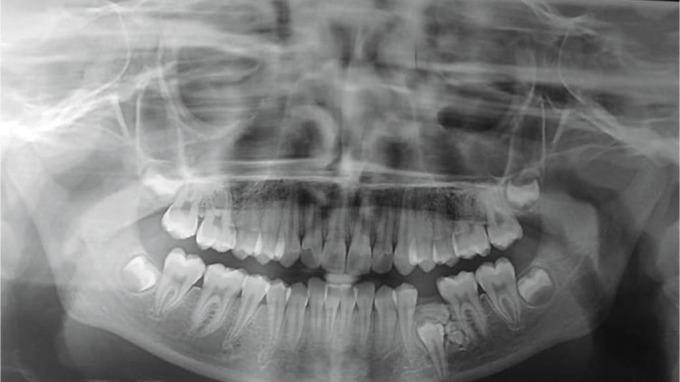

一名13岁女孩下颌阻生前磨牙合并复合-复杂牙瘤:病例报告

Impacted Mandibular Premolar Concomitant with Compound-Complex Odontome in a 13-year-old Girl: A Case Report.

Odontomas, the benign odontogenic tumors of epithelial and mesenchymal origin, are very common in occurrence and are now widely accepted as hamartomas. Odontomes are invariably composed of enamel and dentin, and may also have variable amounts of cementum and pulp. Largely, odontomas have been categorized into the compound and complex varieties. Compound odontoma epitomizes itself as aberrations with the presence of all types of dental tissues and showing an orderly distribution in the form of tooth-like structures; whereas complex odontoma describes itself as aberrations in which the presence of some or all dental tissues and in a disorganized distribution. Herein, a case of compound-complex odontome associated with the impaction of a mandibular second premolar is being presented in a 13-year-old girl.

牙瘤是上皮和间充质来源的良性牙源性肿瘤,发病率很高,目前被广泛认为是错构瘤。牙瘤总是由釉质和牙本质组成,也可能含有不同量的牙骨质和牙髓。牙瘤在很大程度上已被分为复合性和复杂性两种类型。复合性牙瘤表现为所有类型的牙体组织均存在异常,且呈牙样结构有序分布;而复杂性牙瘤则表现为部分或全部牙体组织存在异常且分布紊乱。本文报告了一名13岁女孩,患有与下颌第二前磨牙阻生相关的复合 - 复杂性牙瘤。